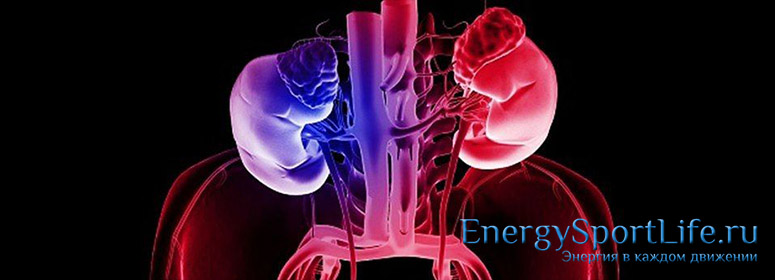

Выделительная система

Выделительная система – выводит из организма исходные продукты обмена веществ, предотвращая его отравление. Выделение вредных веществ происходит с помощью легких, кожи, печени и почек. Основная, это мочевыделительная система.

Мочевыделительная система состоит из следующих органов :

— 2 почки;

— 2 мочеточника;

— Мочевой пузырь;

— Мочеиспускательный канал.

Мочеполовая система в анатомии тела человека

В некоторых научных источниках мочеполовую систему рассматривают как 2 составляющие: мочевыделительную и репродуктивную, однако, из-за тесной взаимосвязи и смежного расположения их всё же принято объединять. Строение и функции этих органов сильно разнятся в зависимости от половой принадлежности, поскольку на них возложен один из самых сложных и загадочных процессов взаимодействия полов — репродукция.

И у женщин, и у мужчин мочевыделительная группа представлена следующими органами: